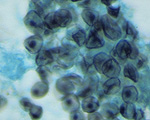

Paracoccidioides brasiliensis Pb18

|

[ Opisthokonta | Fungi | Dikarya | . . .

. . . | Onygenales incertae sedis | Paracoccidioides | Paracoccidioides brasiliensis ]

Picture Source

Picture Source

|

| Taxonomy: | Eukaryota | Opisthokonta | Fungi | Dikarya | Ascomycota | saccharomyceta | Pezizomycotina | leotiomyceta | Eurotiomycetes | Eurotiomycetidae | Onygenales | Onygenales incertae sedis | Paracoccidioides | Paracoccidioides brasiliensis |

| Synonym: | Loboa loboi, Aleurisma brasiliensis (obsolete), Blastomyces brasiliensis (obsolete), Coccidioides brasiliensis (obsolete), Coccidioides histosporocellularis (obsolete), Lutziomyces histosporocellularis (obsolete), Monilia brasiliensis (obsolete), Mycoderma brasiliensis (obsolete), Mycoderma histosporocellularis (obsolete), Zymonema brasiliense (obsolete) |

| Comment: | Paracoccidioides brasiliensisis dimorphic and the causative agent for paracoccidioidomycosis, a chronic granulomatous disease of mucous membranes, skin, and pulmonary system. In contrast to the other yeasts, particularly Blastomyces, Paracoccidioides has multiple buds, a thin cell wall, and a narrow base. |

|

|

|

Go to NCBI Taxonomy (502780) |

|

|

|  |

Encyclopedia of life |

|

|  |

Wikipedia |

| Publication: |

Desjardins CA, Champion MD, Holder JW et. al.

( 2011)

PLoS Genet 7, e1002345.

|

|